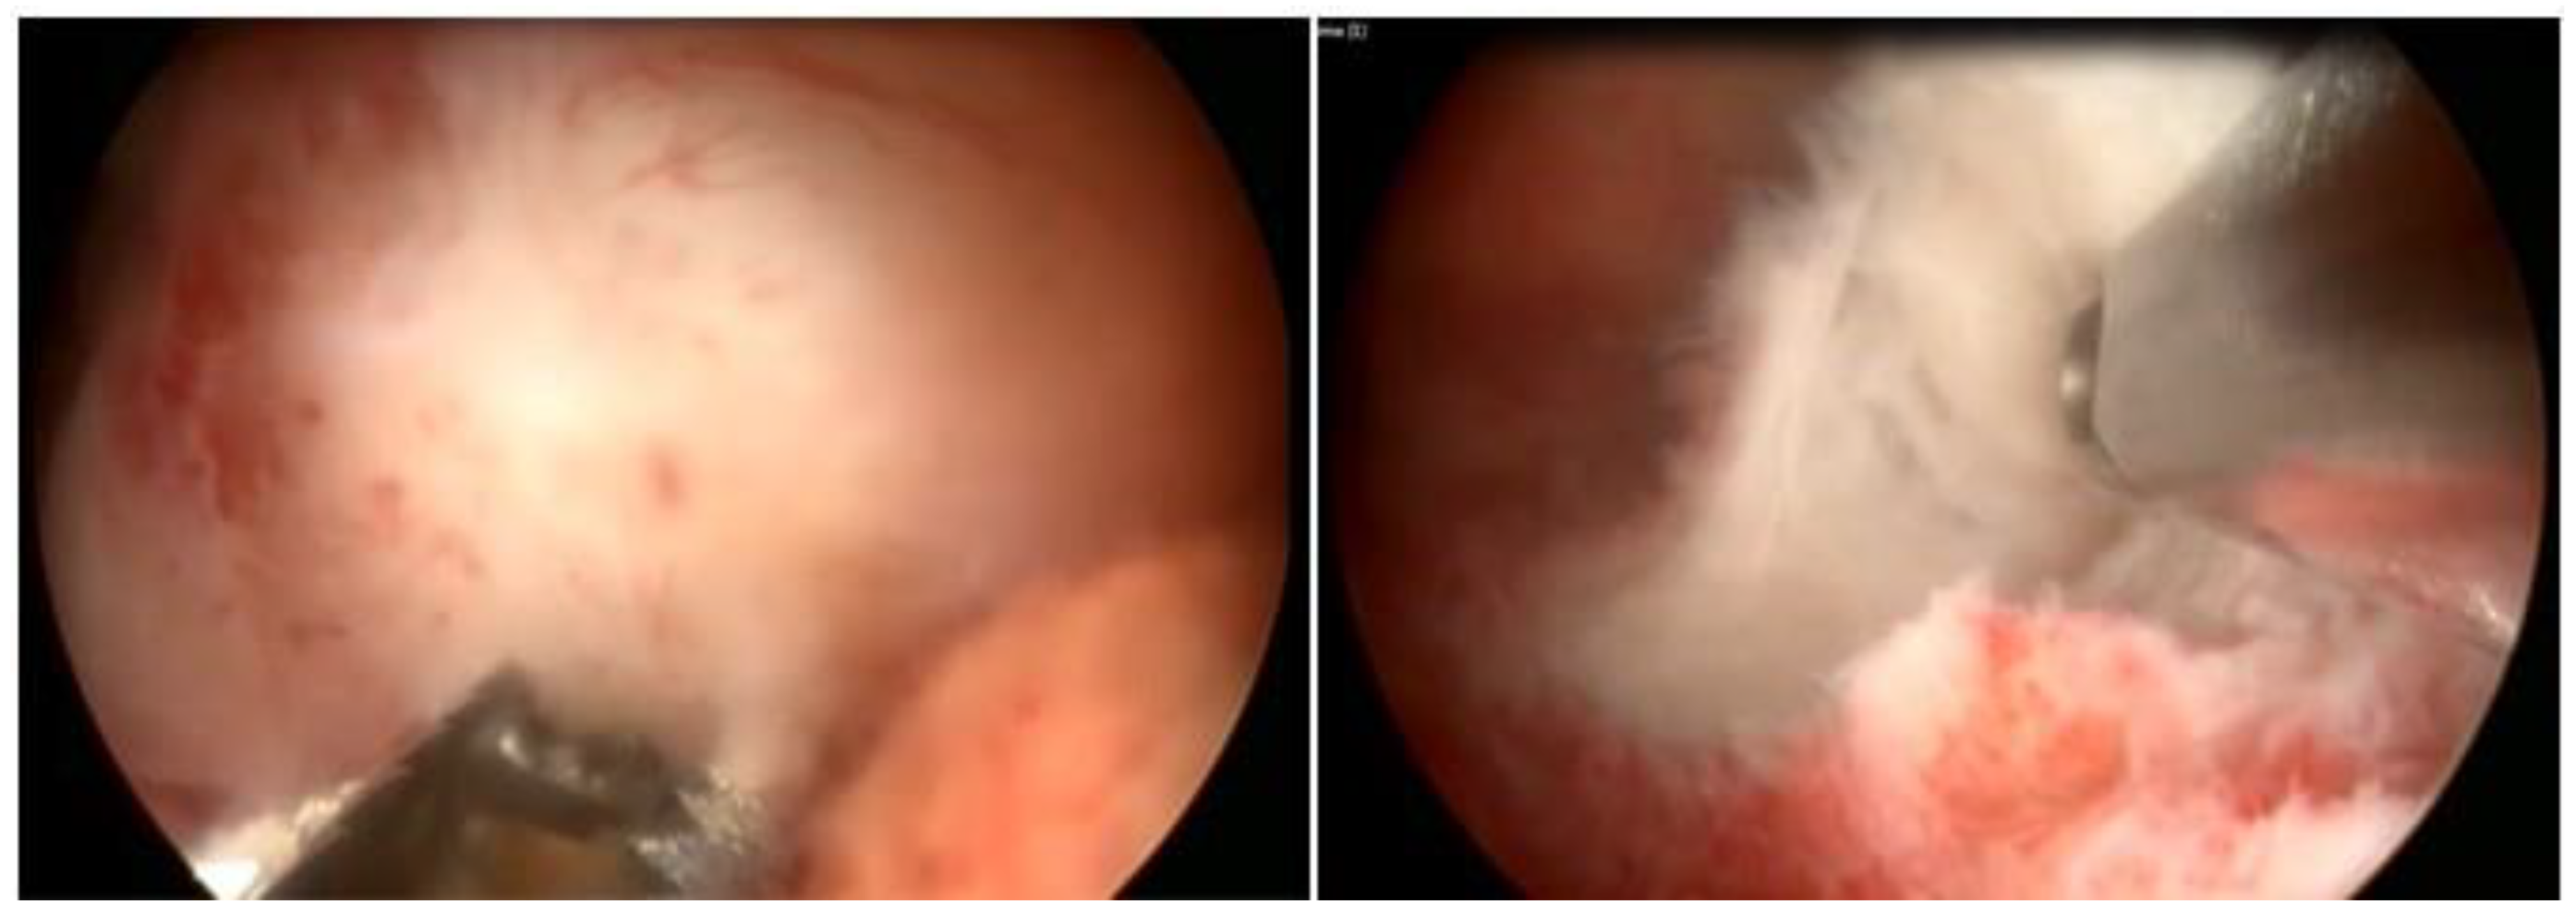

In our service, the most performed technique is using the 5 Fr tweezers or scissors. Initially, the endometrium is incised around the nodule until accessing the plane of the pseudocapsule; then, with the forceps or the body of the hysteroscope, entering between the nodule and the myometrium, the release is initially performed, laterally first and then centrally, until its complete release (Figure 7).

At the end, the nodule will be loose in the cavity and can be fragmented or completely removed with grasping forceps. In cases of difficulty in removing the nodule from the cavity, the patient should be instructed to return in 7 to 10 days, during which time either the nodule will be spontaneously expelled by the patient—she should be oriented about this possibility—or it will have drastically decreased in size, allowing its removal.

Figure 7. Office hystreroscopic myomectomy with scissor.